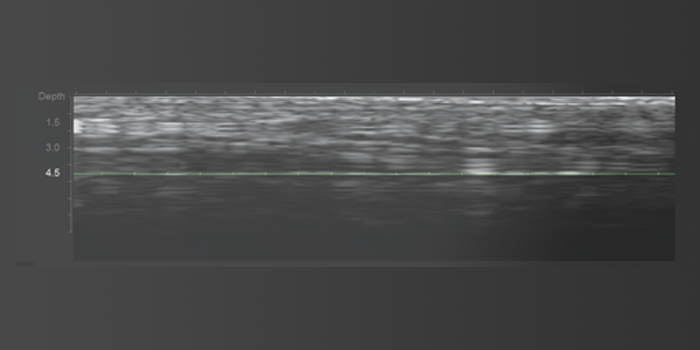

Customized treatments are possible

with 3D visualization of skin layers.

Three transducer optionsโ1.5mm, 3.0mm, and

4.5mmโallow for tailored treatment based on skin thickness and specific treatment goals.

Ultherapy Prime Tip Ultrasound Energy Delivery Location

1.5mm – Epidermis layer

3.0mm – Dermis layer

4.5mm – SMAS fascia layer

Safe Treatment

Real-time skin layer

monitoring reduces

the likelihood of side

effects such

as nerve damage

and cheek indentation.

Accurate Targeting

Precise energy delivery

to the targeted area

with accurate

location selection.

Effective

Effective energy reaches

the correct skin layer,

increasing the

lifting effect.